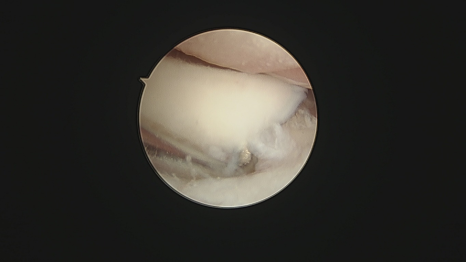

수술은 관절경을 이용하여 진행되었습니다.

팔꿈치 부위에 약 2~3mm 크기의 작은 구멍 생성

초소형 카메라를 통해 관절 내부 실시간 확인

통증을 유발하는 뼛조각 찾아낸 후 제거

손상된 연골 및 염증 조직 정리

대형견 강아지 관절경 수술 사진/ 출처: 에스동물메디컬센터

강아지 FMCP 관절경 진단 출처; 에스동물메디컬센터접기/펴기

관절경 수술은 주변 조직 손상을 최소화하기 때문에 수술 후 통증이 훨씬 적고, 회복 속도가 빠르다는 장점이 있습니다.